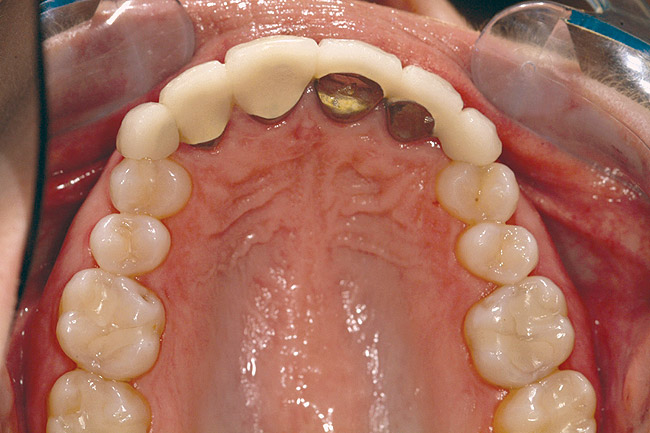

Fig 2 (and Fig 3). Corticotomy SFOT. The patient presented with unesthetic anterior bridgework that was placed at age 14 to compensate for congenitally missing Nos. 7 and 10.

Figure 2

Fig 3 (and Fig 2). Corticotomy SFOT. The patient presented with unesthetic anterior bridgework that was placed at age 14 to compensate for congenitally missing Nos. 7 and 10.

Figure 3

Fig 4. Note gingival inflammation caused by biologic width violation. Provisional restorations were placed on Nos. 6, 8, 9, and 11, and corticotomies were performed from Nos. 3 to 14.

Figure 4